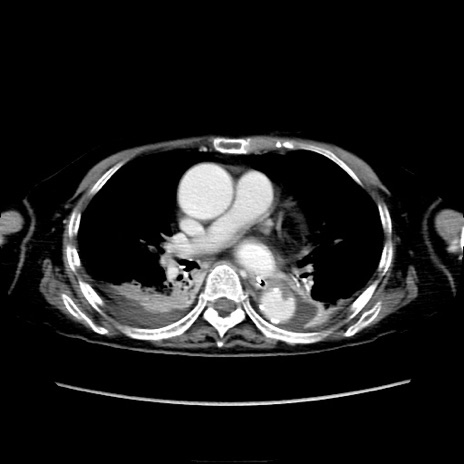

症例40(横断像)

【症例】90歳代女性

【主訴】腹痛・嘔吐

【現病歴】 食欲低下、嘔吐があり昨日他院受診。肺炎と診断され入院となる。入院後より腹部全体に圧痛あり。胃管留置され経過みていたが、症状持続するため、

当院転院となる。

【既往歴】胸椎圧迫骨折、胆石症

【身体所見】腹部:中央に激痛あり、圧痛あり、反跳痛不明

【データ】WBC 17100、CRP 18.82

他院CT

横断像